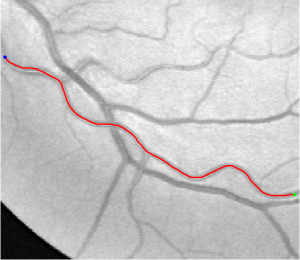

Validation. We validate our minimal path model on respective 54 and 30 patches obtained from the DRIVE [14, 15] and the IOSTAR [16] datasets with AV groundtruth. Each artery involved in these parches locates near a vein or crossing it at least once. Our goal is to extract the artery between two given points. In order to get the quantitative evaluation, we first convert each continuous spatial path to an 4-connected digital path which is considered as a pixel collection. We denote by the collection of digital path pixels inside the artery groundtruth map . Thus, a measure can be simply defined as , where and mean the respective number of elements involved in and . We compare our model to four existing minimal path models: the isotropic Riemannian (IR) model [1], the anisotropic radius-lifted Riemannian (ArR) model [4], the isotropic orientation-lifted Riemannian (IoR) model [5] and the curvature-penalized (CuP) model [7]. The construction of these metrics are based on the OOF outputs [12]. Note that a centerline-based potential is chosen so that we remove the radius dimension of [5] to reduce computation complexity. The results in terms of the score are presented in Table 1, including the average (Avg.), maximum (Max.), minimum (Min.) and standard deviation (Std.) values. In both DRIVE and IOSTAR datasets, our method can achieve the best performances thanks to the coherence penalization. Note that in Table 1, we evaluate our method by using the refined paths instead of using the original coherence-penalized minimal paths. For comparisons in visualization, we show the minimal paths from the ArR metric , the CuP metric and the proposed coherence-penalized metric on three retinal patches as shown in Fig. 3. The targeted artery vessels which cross veins at least once are labeled by red color in column 1. The paths shown in column 4 from the proposed metric are results after refinement. One can claim that our method indeed can catch expected arteries while other metrics fall into the traps of short branches combination.